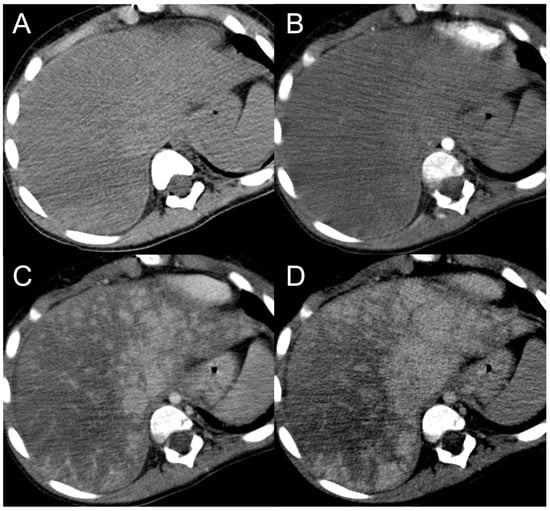

Figure 8.

CT examination of a 5-year-old female patient with Budd–Chiari syndrome revealing a pseudo-lesion caused by hypertrophy of the caudate lobe. The caudate lobe (arrows) shows slight hyperdensity on unenhanced images (A), with heterogeneous contrast enhancement in the arterial (B), portal (C) and delayed phase (D). Notably, this represents a normal enhancement pattern due to preserved venous drainage, in contrast to the surrounding congested liver parenchyma. The hypertrophied caudate lobe also causes compression on the stomach (arrowheads), contributing to its mass-like appearance.